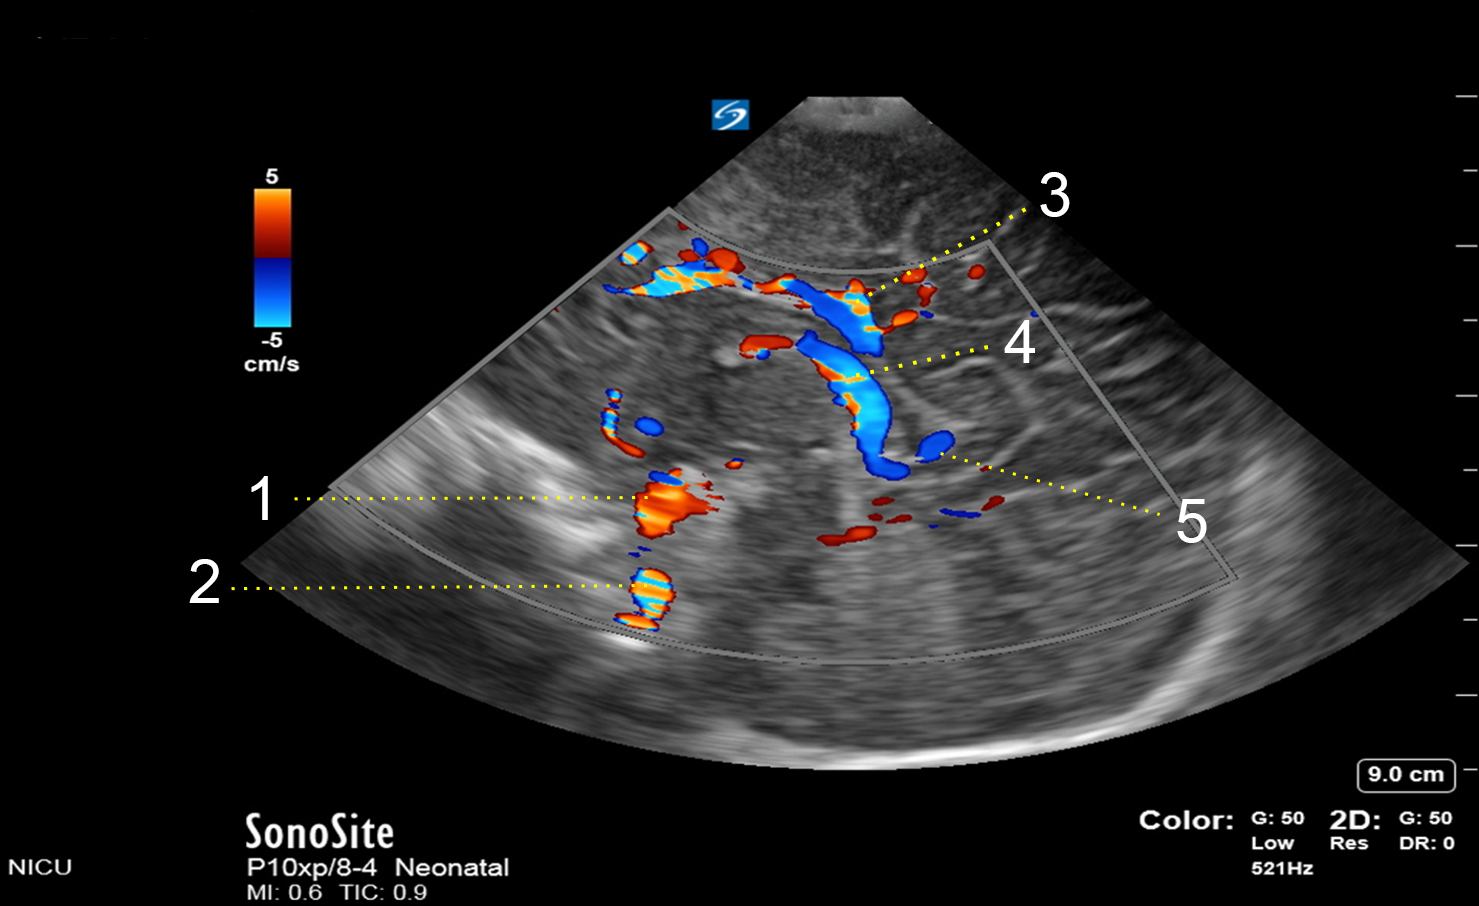

1. Anterior Cerebral Artery (ACA)

2. Internal Carotid Artery (ICA)

3. Inferior Sagittal Sinus (ISS)

4. Internal Cerebral Vein (ICV)

5. Vein of Galen (VOG)